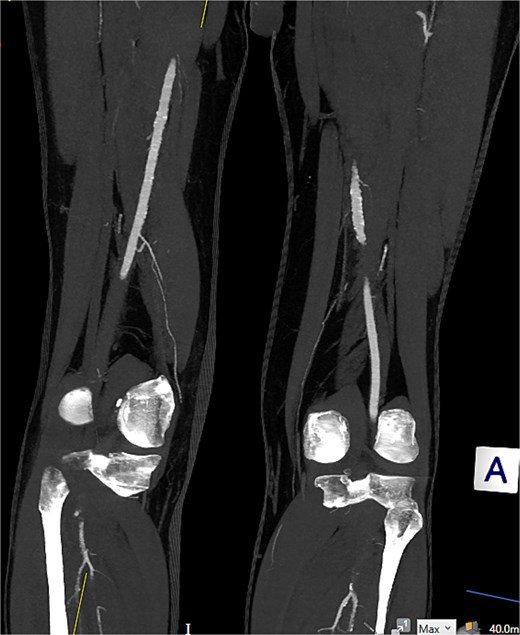

Computed tomography (CT) angiography (Figs 1 and 2) revealed a near-occlusive filling defect at the left common iliac bifurcation. Further embolic material extended into the left common femoral bifurcation, profunda femoris, and superficial femoral artery. An embolic occlusion was also present in the below-knee popliteal artery, extending to the trifurcation, with partial reconstitution of the calf vessels. Emboli were seen in the posterior tibial and peroneal arteries. On the right side, embolic material was noted in the distal profunda and popliteal artery, with further emboli in the tibio-peroneal trunk. The patient underwent bilateral femoral thromboembolectomy.

Embolic occlusion of the below-knee popliteal artery extending to the trifurcation, with partial reconstitution of the calf vessels. Emboli are also present in the posterior tibial and peroneal arteries.